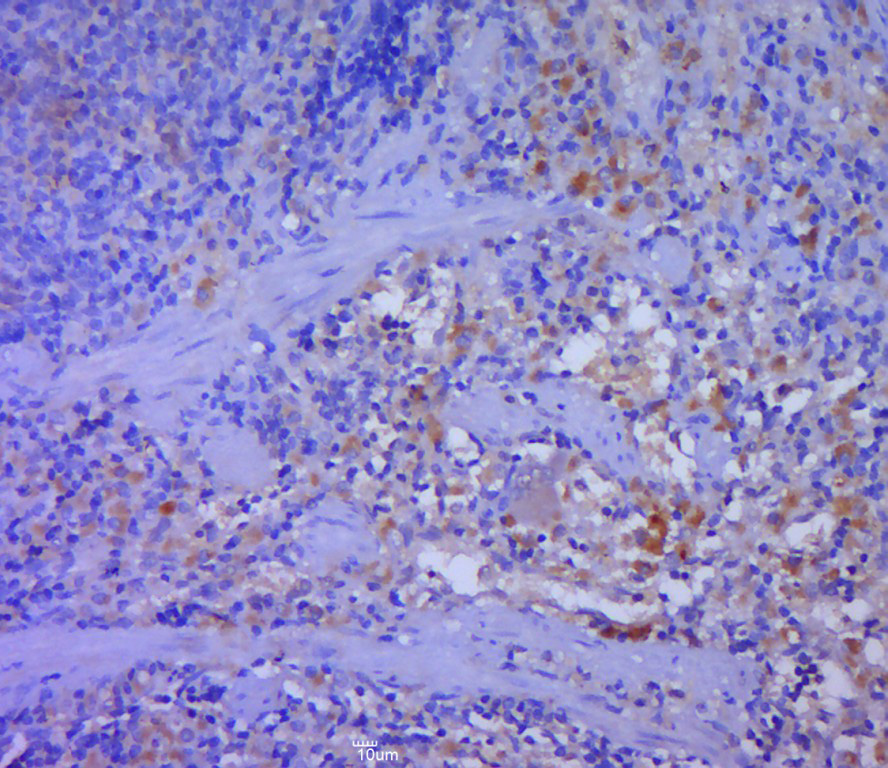

Primary: rabbit Anti-DFNA5 (bs-14286R) at 1:300;

Secondary: HRP conjugated Goat-Anti-rabbit IgG(bs-0295G-HRP) at 1: 5000;

Predicted band size: 54 kD

Observed band size: 54 kD